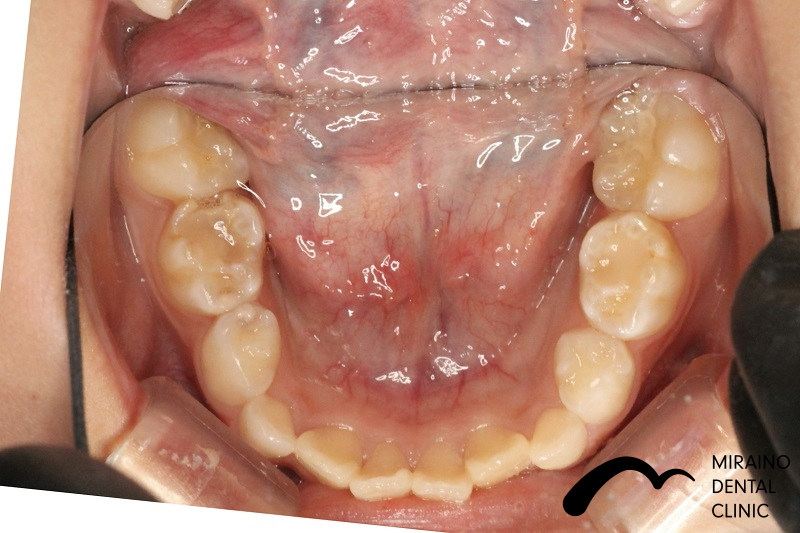

過蓋咬合①

| 施術名 | マウスピース矯正(インビザライン) |

| 施術の内容 | 歯科矯正でも目立ちにくい新しい矯正方法です。 透明に近いマウスピース型の矯正装置(アライナー)のため、歯に装着しても目立つことなく歯並びを矯正することが出来ます。 また、一人ひとりの合わせて矯正装置を作製いたします |

| 治療費 | インビザライン990,000円 |

| 考えられるリスク、副作用 | 疼痛・咬合時痛を生じる事があります。時間経過とともに治ります。 |

| 考えられるリスク、副作用[矯正] | 継続使用により緩んだり、外れやすくなる事があります。 割れたり壊れたりする事があります。諸々の事情により、治療期間が当初よりも伸びる事があります。 所定の装着時間22時間を守って頂けない場合、治療計画どおりに治らない可能性があります。 歯が動く際に、痛みが出る事があります。 矯正期間中は虫歯や歯周病のリスクが高まりますので、しっかりとしたケアが必要です。 歯の移動に伴う歯肉退縮や歯根吸収が起こる事があります。 インビザライン・システム(invisalignR)は、アメリカのアラインテクノロジー社より提供されている、カスタムメイドの矯正装置ならびに、これを用いた治療システムを指します。 インビザラインを用いた治療は保険適用外の自由診療となります。 厚労省の認可(医薬品医療機器等法上の承認)は得ていないため、まだ明らかになっていないリスクが存在する可能性があることをご了承ください。 |

| 全て | 必ずしもご希望通りの見た目にならない事があります。 |